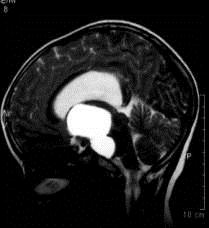

问题 病历摘要:??患者女性,6岁,半年来感觉视力模糊,近10天出现反复头痛,间有恶心呕吐,精神转差,查体:神志清楚,身高90cm,体重25Kg,血压90/55mmHg,右眼视力4.6,左眼视力4.8,双侧视乳头水肿,颈软,伸舌居中,四肢肌张力正常,肌力5级,双侧Babinski征(-)。 患者具有下列那些表现,可以诊断抗利尿激素分泌不当综合征?